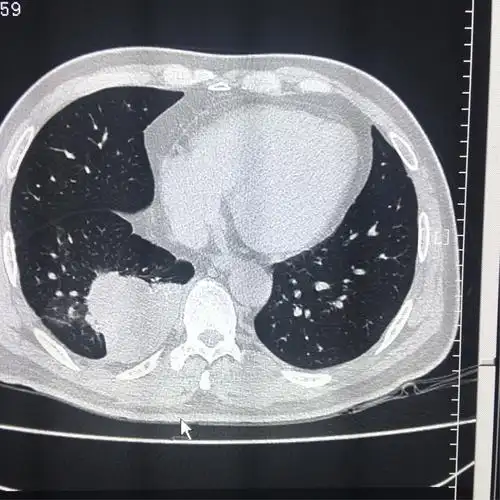

肺隔离症影像表现_郑孝飞

右肺下叶肺隔离症一例-中国期刊网

年轻女子咳嗽,咳痰2年,病因不寻常……_肺隔离症_医脉通

肺隔离症

肺隔离症诊断之影像与病理